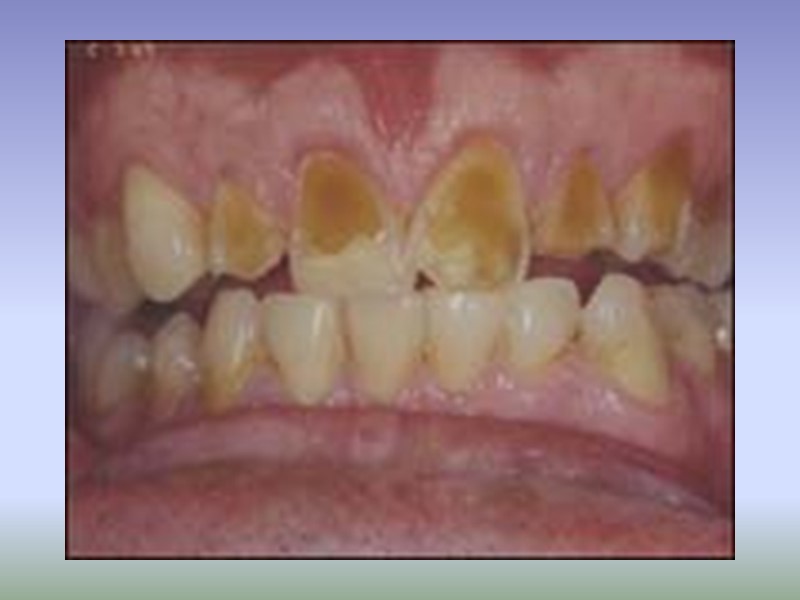

Начальный кариес дифференцируют: флюорозом (пятнистой формой) системной гипоплазией (пятнистой формой) местной гипоплазией (пятнистой формой).

Дифференциальная диагностика кариеса в стадии пятна с гипоплазией и флюорозом Общее: наличие пятен на эмали, эстетический дефект

Поверхностный кариес дифференцируют с: Системной гипоплазией (бороздчатая форма) Флюорозом (эрозивная форма) Эрозией эмали Клиновидным дефектом Кислотным некрозом

Дифференциальная диагностика поверхностного кариеса с гипоплазией и флюорозом Общее: наличие дефекта твердых тканей в пределах эмали, эстетический дефект